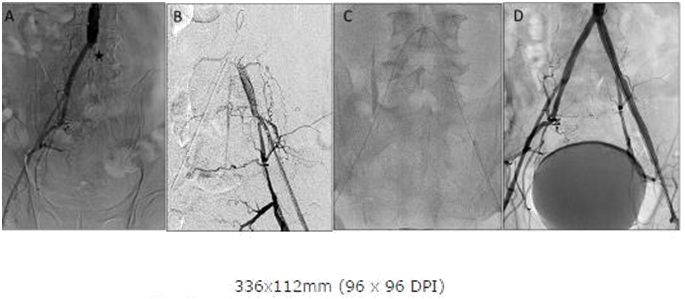

Right Common Femoral Artery (CFA) access was obtained and abdominal angiogram revealed a left proximal Iliac occlusion (Figure 1A) with reconstitution at the left femoral bifurcation (Figure 1B). Left CFA access was obtained with fluoroscopic guidance and a 6 Fr sheath placed in the Left CFA. Attempts were made with a 0.035 angled glidewire through the 6 Fr sheath from below but were unsuccessful in crossing the distal cap of the occlusion and a the wire was noted to enter a subintimal plane. A CC was advanced from the Right CFA and pulled down to firmly clip the aortic bifurcation (Figure 1C). A 0.035 stiff angled glidewire was then slowly advanced through the PICTO from the CC above without catheter back out and able to exit into the true lumen below. The wire was then snared and externalized through the Left CFA sheath. Once the wires were positioned true lumen to true lumen, the rest of the case was finished using standard stenting techniques and the left PICTO was recanalized with an excellent angiographic result (Figure 1D). The patient was claudication free at 1 month follow up without any complications.

Figure 1A: Abdominal Aortogram showing Left Common Iliac occlusion and proximal cap (asterisk). Note previous stent in Left common iliac.

Figure 1B: Angiography from sheath inserted in Left femoral showing dissection due to attempts at retrograde crossing from left.

Figure 1C: Contra catheter with angled glide from right seated at bifurcation with clip like action providing support for crossing occlusion.

Figure 1D: Abdominal Aortogram post stenting showing good angiographic result.